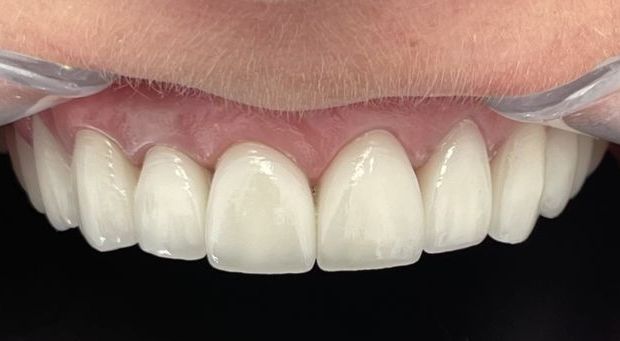

Pełna rekonstrukcja zgryzu, zmiana koloru i kształtu zębów za pomocą koron i mostów cyrkonowych licowanych porcelaną w kolorze BL2.